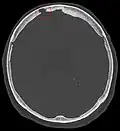

Non-contrast CT scan of the head showing an arachnoid granulation